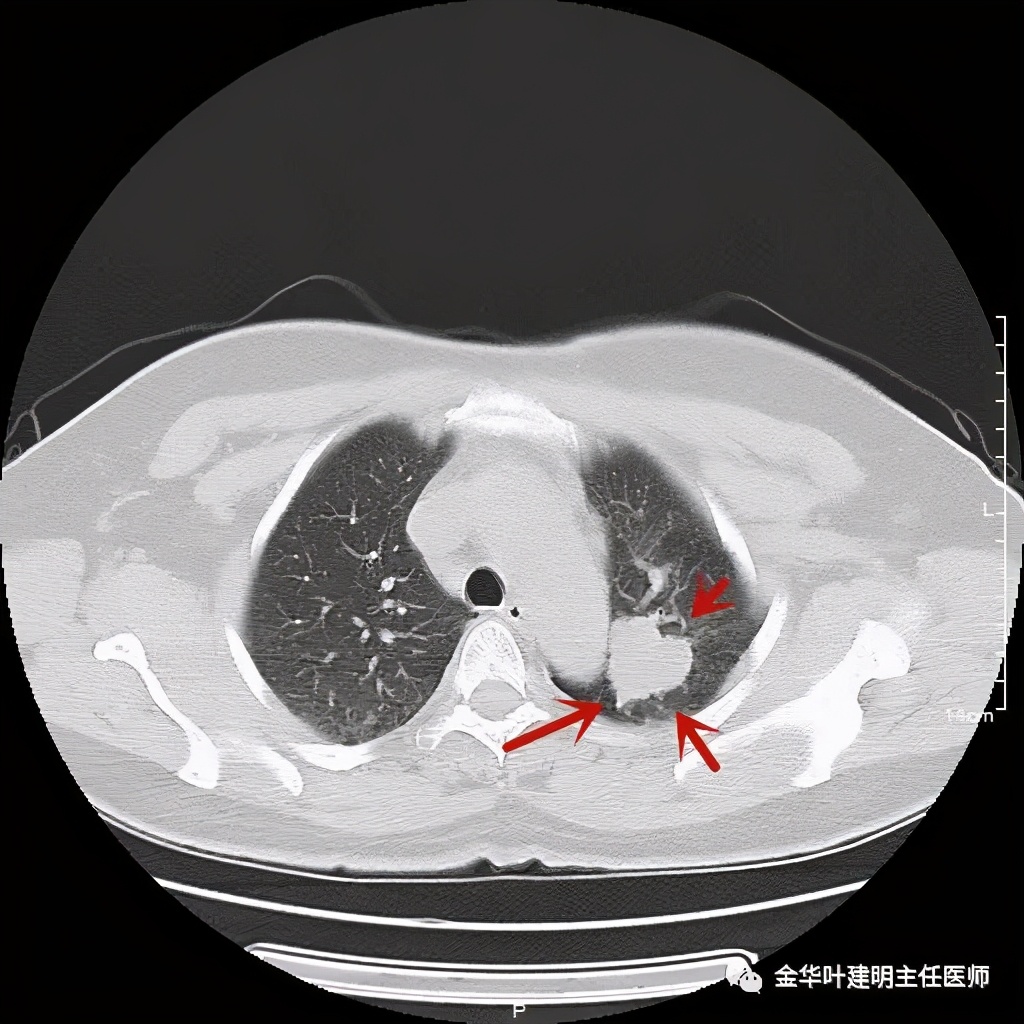

七、浸润性腺癌的其他型:

上图病例为实性,病理上实体型占80%,腺泡型占20%

上图此例也是实性结节,病理报告:实体型伴神经内分泌;

上图此例的实性肿块,病理是:微乳头为主,部分实体型,当时没注明占比;

上图此例实性结节,是实体型,我们发现其影像特征: 病灶有浅分叶、细毛刺、支气管截断征、膨胀性,密度高而密 (比腺泡型实、比粘液癌高、比鳞癌或小细胞癌更具膨胀性)。

但是上面这几例,因为不管怎样的组合,都是实性密度+实性密度,这时仅从影像上就非常难以判断具体的亚型,不过,我们要根据相关的影像特征判断它为恶性,而且该尽早取得病理依据,能手术的要抓紧、不能手术的也要穿刺等得到病理类型的确诊后积极治疗,这就够了!